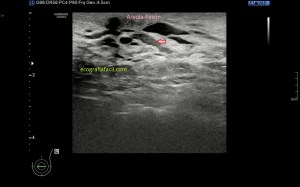

En el caso que te traigo hoy no hizo falta buscar mucho, nada más poner la zona en corte transverso en la región inguinal derecha, cerca de los labios mayores, la paciente tenía una masa blanda, ligeramente dolorosa durante la exploración que había aumentado ligeramente tiempo atrás y que ecográficamente tenía un aspecto anecoico,imagen 1, de paredes finas, más grande en su eje lateral que en el eje antero posterior y que se deformaba con la ligera presión del transductor y que no modificaba su ecoestructura con la maniobra de Valsalva.

En cuanto localicé este hallazgo realicé corte transverso (imagen 2) y longitudinal (imagen 1), con medidas y estudio en modo doppler para ver vascularización (imagen 3, flecha amarilla), seguidamente, era muy importante asegurar algunas referencias locoregionales como los grandes vasos femorales, siempre debemos documentar esta coexistencia y buscar un cuello que puedes observar con las dos flechas rojas de la imagen 1 y que la ecoestructura marca perfectamente al ser anecoica.

Aunque no muchas, ya había visto alguna vez esta entidad y sabía que era un Quiste de Nuck, pero necesitaba buscar los hallazgos anatómico ecográficos previamente comentados, como la localización junto a los grandes vasos y el cuello, para poder presentarlo a la radióloga para que realizase el informe, que corroboró lo que pensaba, lo cual no tiene relevancia alguna. Esta patología puede ser conocida también como Hidrocele de Nuck.

1

2

3